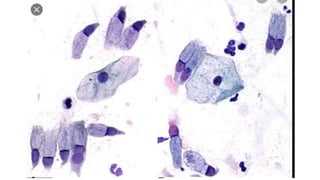

Células Escamosas

Células Glandulares